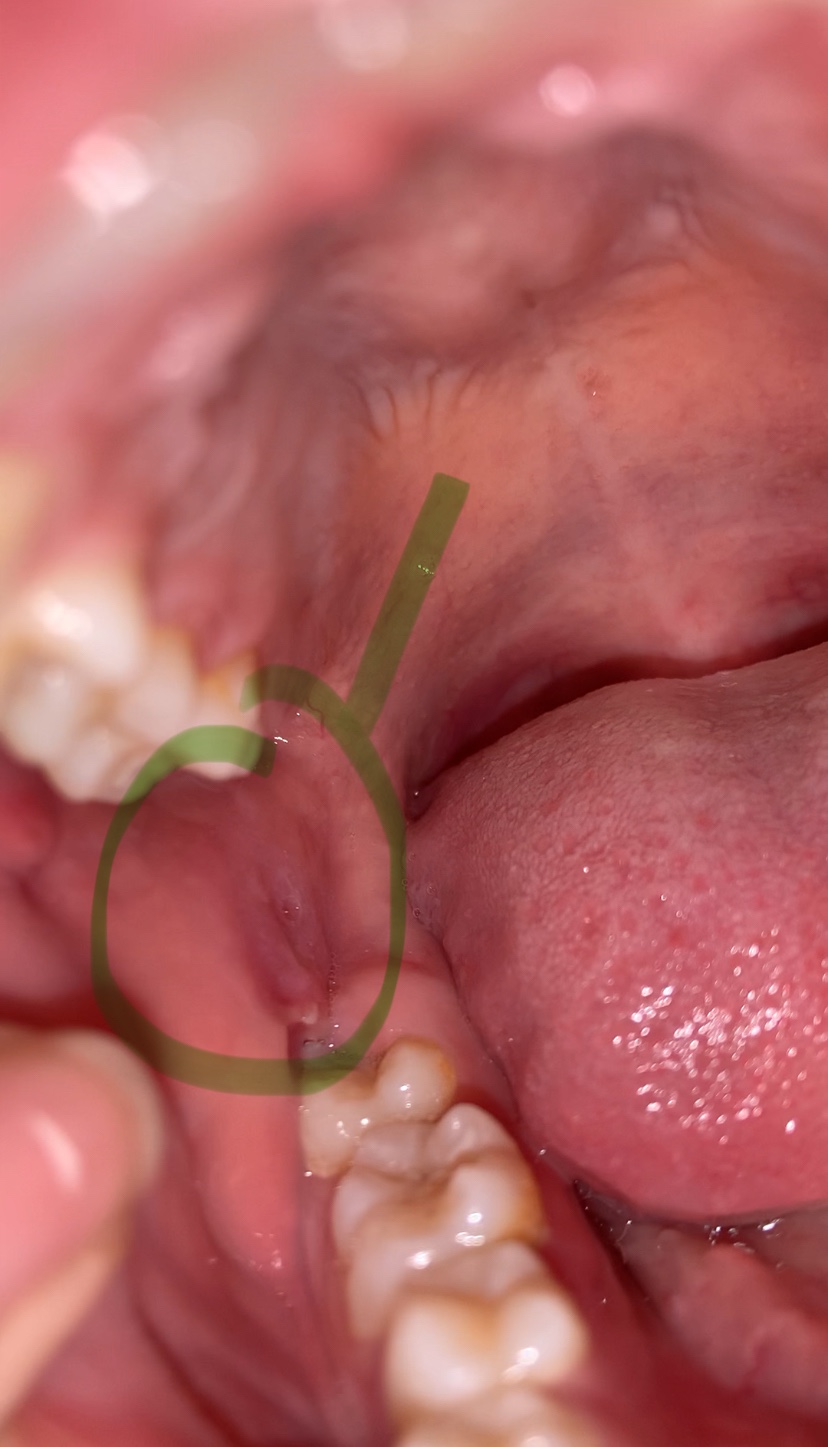

แบบนี้คือเป็นอะไรหรอคะ

มันเจ็บๆ เหมือนเนื้อมันกดลงไป แบบนี้เขาเรียกว่าเป็นอะไรคะ แล้วทำยังไงให้มันหาย